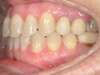

Cas 2 : Description

Tendance prognathisme.Traitement par gouttières.

Avant

Après